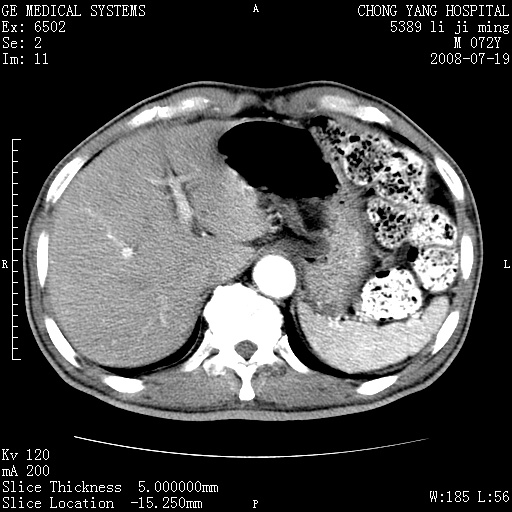

以下是引用zjzjr在2008-7-19 20:57:00的发言:[br]胰头增大,边缘模糊,周围可见渗出影,右侧肾前筋膜增厚.支持胰腺炎.

以下是引用yangyudong333在2008-7-20 6:56:00的发言:[br]胰腺增大尤以胰头明显,边缘模糊,周围可见渗出影,右侧肾前筋膜增厚,肠管於涨.支持胰腺炎

以下是引用不学无术在2008-7-19 23:15:00的发言:[br]胰腺增大尤以胰头明显,边缘模糊,周围可见渗出影,右侧肾前筋膜增厚,肠管於涨.支持胰腺炎